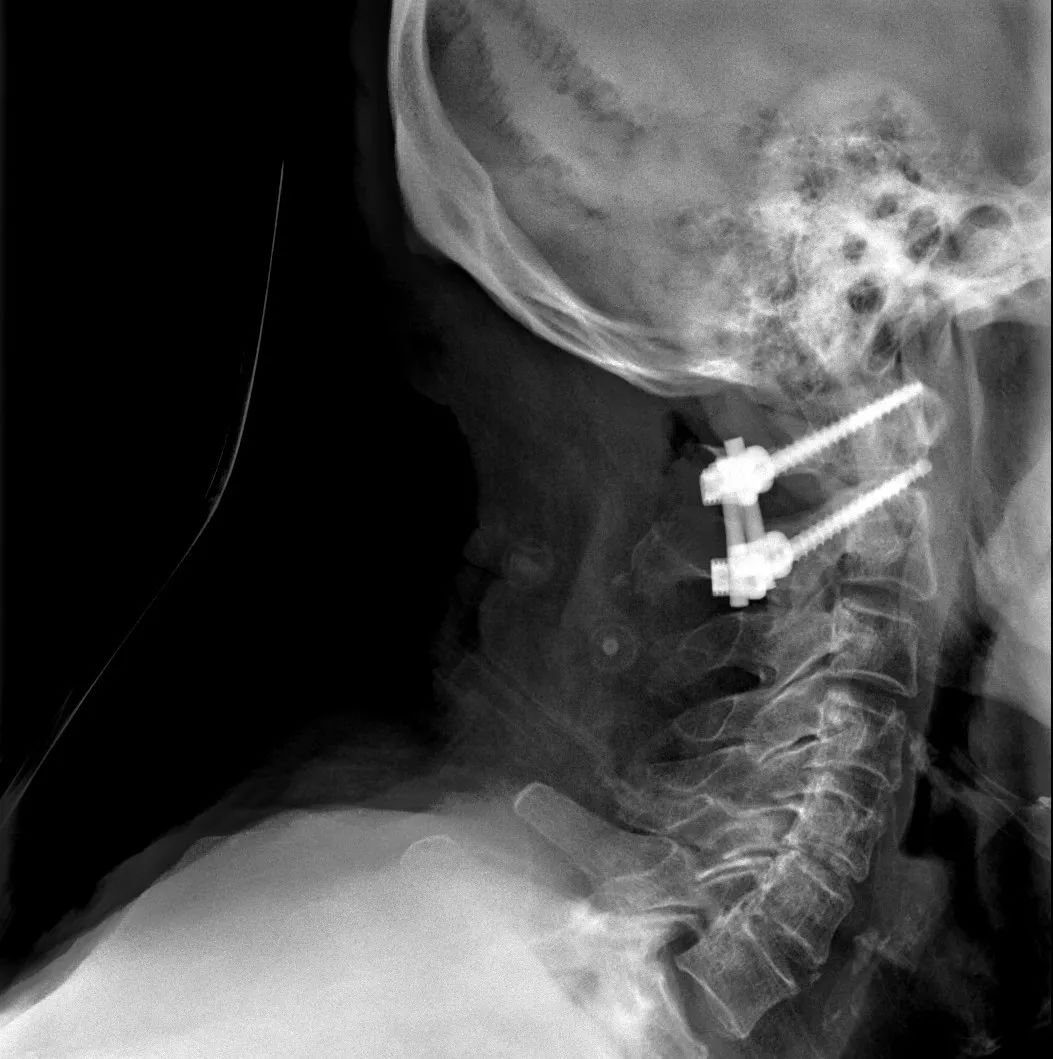

经过全程监护和系统治疗,患者术后恢复良好,骨折解剖复位,复查X线及CT显示固定位置佳,术后3天下地行走,术后4天即出院回家休养。

该手术为我市首例完成C1、2椎弓根钉棒系统固定手术,填补了枣庄在上颈椎外伤手术史上的空白,展现了枣庄市立医院脊柱外科不怕困难、勇于突破、积极向上的精神面貌,也是王存平主任技术高超、胆大心细的具体体现。